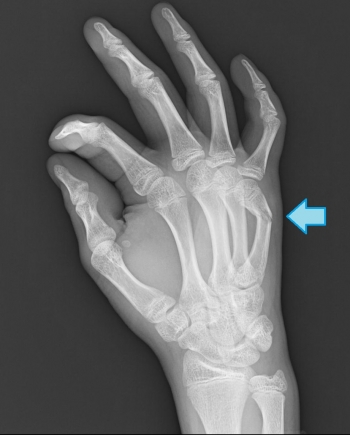

º£Æü¡¢¤´¾Ò²ð¤¹¤ë¤Î¤Ï¡¢¼ê»Ø¹ü¹üÀÞ¤ÎʬÎà¤Î¾ÜºÙ¤Ë¤Ä¤¤¤Æ¤´¾Ò²ð¤·¤Æ¤¤¤­¤¿¤¤¤È»×¤¤¤Þ¤¹¡£

¼ê»Ø¹üÀÞ¤ÎʬÎà

´ðÀá¹ü¹üÀÞ

­¡¹ü´´Éô¹üÀÞ¡¡­¢¹üƬ¡¦·ÛÉô¹üÀÞ¡¡­£´ðÄìÉô¹üÀÞ

Èæ³ÓŪÉÑÅ٤ι⤤¹üÀޤǤ¹¡£

´°Á´¹üÀޤξì¹ç¤Ï¡¢¤·¤Ð¤·¤ÐÄ귿Ū¤Ê¾¸Â¦ÆÌÊÑ·Á¤Ë¤Ê¤ë¡£

¥¹¥Ý¡¼¥Ä¤Ë¤è¤ë²á¿­Å¸¤ä²á¶þ¶Ê¤Ë¤è¤ë»½ý¤¬Â¿¤¤¡£

¹ü´´Éô¹üÀÞ

¶á°Ì¹üÊÒ¤ÏÃîÍͶڤä¹ü´Ö¶Ú¤Ë¤è¤ê¶þ¶Ê¡¢±ó°Ì¹üÊÒ¤ÏÇØÂ¦ç§Ëì¤Ë¤è¤ê¾¸Â¦ÆÌ¤Ëž°Ì¤¹¤ë¡£

¹üƬ¡¦·ÛÉô¹üÀÞ

ÉÑÅ٤Ȥ·¤Æ¤Ï¹â¤¯¤Ê¤¤¤Ç¤¹¤¬¸«Æ¨¤µ¤ì¤ä¤¹¤¯¡¢¾®»ù¤Ë¿¤¤¹üÀÞ

¹üÀÞ¤·¤¿¹üƬÉô¤Ï¡¢¹üÀÞü¤ò¾¸Â¦¤Ë¸þ¤±¤Æ£¹£°¡ë²óž¤·¡¢Â¦Éû¿ÙÂӤˤè¤ê¹ÊÙ¯¤µ¤ì¤ÆÀ°Éü¤¬º¤Æñ¡£

´ðÄìÉô¹üÀÞ

¾¸Â¦ÆÌ¤ÎÊÑ·Á¤òÄ褹¡£

¾®»ù¤Ë¤Ï¹üüÀþÎ¥³«¤ò¸«¤ë¤³¤È¤â¤¢¤ë¡£